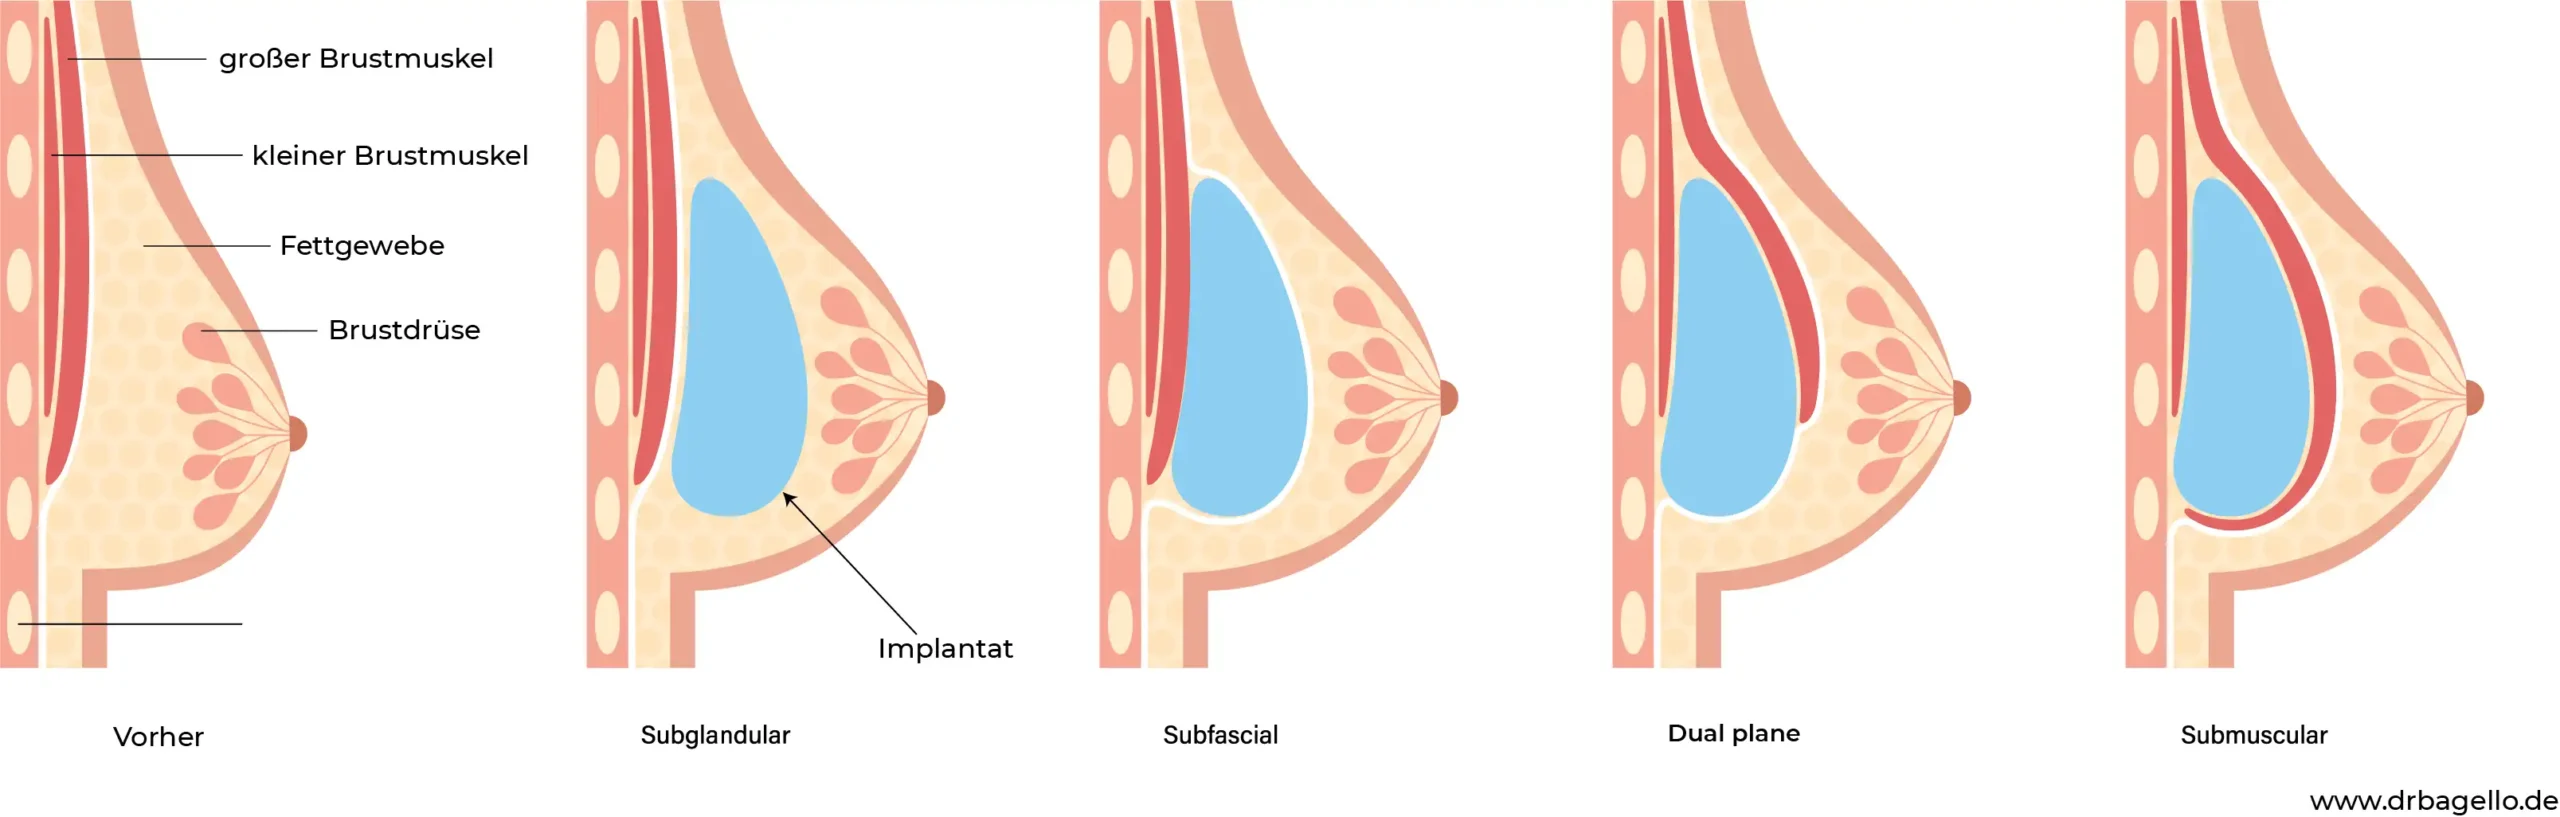

Bei dieser Technik werden die Implantate unter dem Drüsengewebe, auf dem großen Brustmuskel platziert.

Bei dieser Technik werden die Implantate unterhalb der Faszie platziert, die das Brustgewebe umgibt, aber über dem Brustmuskel.

Bei dieser Technik werden die Implantate teilweise unter dem großen Brustmuskel platziert, der als „M. pectoralis major“ bekannt ist. Im oberen Bereich ist das Implantat von dem Muskel bedeckt, was zu einem natürlicheren Ergebnis führen kann und das Risiko von sichtbaren Implantaträndern verringert.

Bei dieser Technik werden die Implantate vollständig unter dem großen Brustmuskel platziert.

Bei dieser Technik werden die Implantate unter dem Drüsengewebe, auf dem großen Brustmuskel platziert.

Bei dieser Technik werden die Implantate unterhalb der Faszie platziert, die das Brustgewebe umgibt, aber über dem Brustmuskel.

Bei dieser Technik werden die Implantate teilweise unter dem großen Brustmuskel platziert, der als „M. pectoralis major“ bekannt ist. Im oberen Bereich ist das Implantat von dem Muskel bedeckt, was zu einem natürlicheren Ergebnis führen kann und das Risiko von sichtbaren Implantaträndern verringert.

Bei dieser Technik werden die Implantate vollständig unter dem großen Brustmuskel platziert.

Es gibt zwei Hauptoptionen für die Platzierung von Brustimplantaten.

Subglanduläre Platzierung (über dem Brustmuskel):

- Vorteil: Oft natürlicheres Bewegungsverhalten der Brust

- Nachteil: Höheres Risiko für sichtbare Implantatränder

Submuskuläre Platzierung (unter dem Brustmuskel):

- Vorteil: Natürlicheres Erscheinungsbild, besonders bei wenig Eigengewebe

- Nachteil: Eventuell längere Erholungszeit

Die optimale Platzierung hängt von Ihrer individuellen Anatomie und Ihren Wünschen ab. Dr. med. Mathias Bargello wird in Ihrem persönlichen Beratungsgespräch die beste Option für Sie empfehlen.